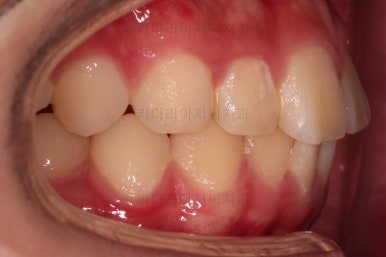

치료 끝!

전체적인 교정을 하지 않아끼 때문에, 완벽히 디테일을 맞추긴 힘들었지만 충분히 기능을 할 수 있게끔 위치를 바로잡아 주었어요.

총 치료기간은 단 5개월!

치료 전후 비교해 볼게요.

5개월이라는 매우 짧은 기간 안에 정확한 치료계획과 고난이도 테크닉으로 매복 사랑니도 발치하고 매복된 어금니도 바로 세워서 잘 사용할 수 있게끔 해드렸습니다.